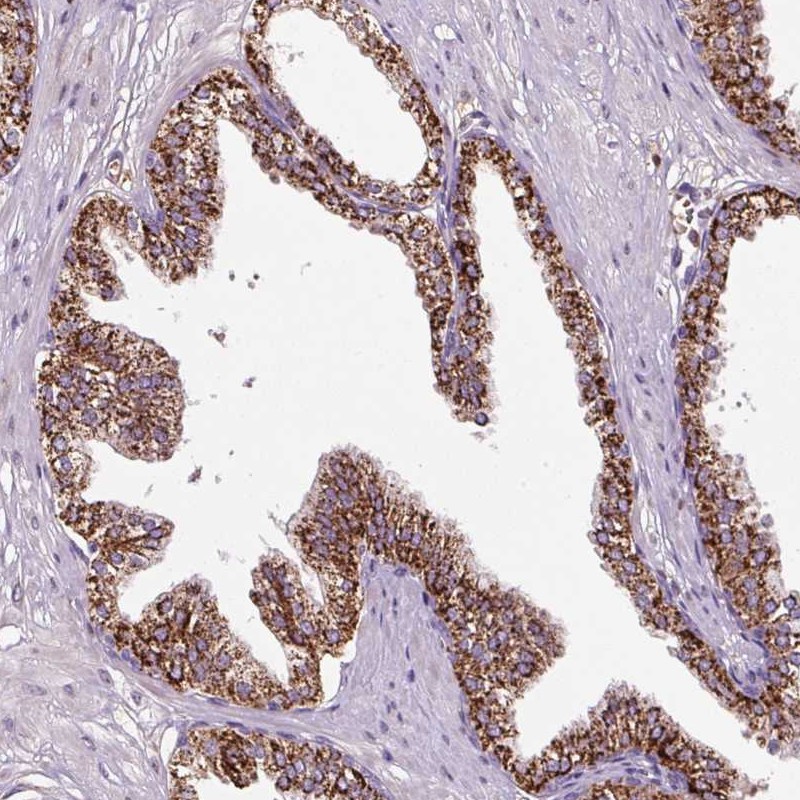

Immunohistochemical staining of human prostate shows strong cytoplasmic positivity in glandular cells.